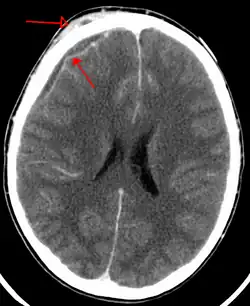

An abscess that has led to an intracranial subdural empyema as seen on CT

Bacterial or occasionally fungal infection of the skull bones or air sinuses can spread to the subdural space, producing a subdural empyema. The underlying arachnoid and subarachnoid spaces are usually unaffected, but a large subdural empyema may produce a mass effect. Further, a thrombophlebitis may develop in the bridging veins that cross the subdural space, resulting in venous occlusion and infarction of the brain. With treatment, including surgical drainage, resolution of the empyema occurs from the dural side, and, if it is complete, a thickened dura may be the only residual finding. Symptoms include those referable to the source of the infection. In addition, most patients are febrile, with headache and neck stiffness, and, if untreated, may develop focal neurologic signs, lethargy, and coma. The CSF profile is similar to that seen in brain abscesses, because both are parameningeal infectious processes. If diagnosis and treatment are prompt, complete recovery is usual.